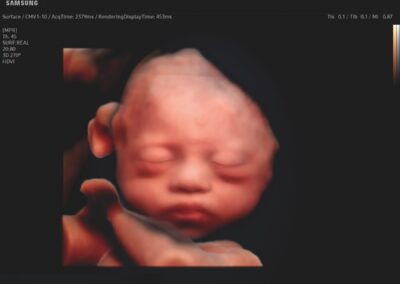

Comprehensive, advanced and expert MFM care for high-risk pregnancies